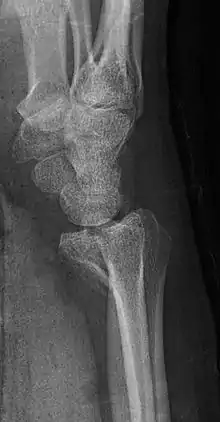

صورة شعاعية إسقاطية جانبية للكسر ذاته.